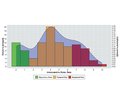

Авторы:

Хмизов С.О., Кацалап Є.С., Карпінський М.Ю., Яресько О.В.

ДУ «Інститут патології хребта та суглобів ім. проф. М.І. Ситенка НАМН України», м. Харків, Україна

Журнал «Травма» Том 22, №4, 2021

Рубрики:

Травматология и ортопедия

Разделы:

Клинические исследования